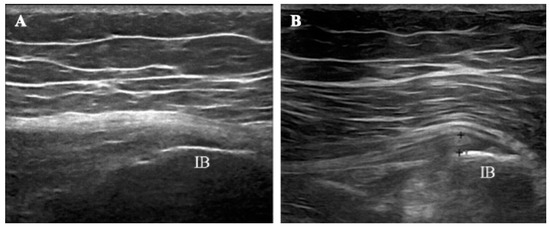

- Manske, R.C.; Wolfe, C.; Page, P.; Voight, M.L.; Bardowski, E. The Utilization of Diagnostic Musculoskeletal Ultrasound in the Evaluation of Gluteus Medius Tendon Pathology: A Perspective for Rehabilitation Providers. Int. J. Sports Phys. Ther. 2024, 19, 642–645. [Google Scholar] [CrossRef] [PubMed]

- Hwang, J.T.; Yoon, K.J.; Park, C.-H.; Choi, J.H.; Park, H.-J.; Park, Y.S.; Lee, Y.-T. Follow-up of Clinical and Sonographic Features after Extracorporeal Shock Wave Therapy in Painful Plantar Fibromatosis. PLoS ONE 2020, 15, e0237447. [Google Scholar] [CrossRef]